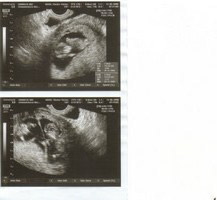

Naše dvojčátka

Na ultrazvuku 20.8.2008 miminkům krásně ťuká srdíčko,melou sebou,i když pohlaví je nejisté,těšíme se na vše....

Prvně jsem myslely,že podle slov pana gynekologa čekáme jednovaječné dvojčátka,pač našel 1 placentu,ale vypadáto,že pam primář ted na UTz ve 20tt našel i druhou...takže by mohla být i naděje na vysněný páreček!

2screening:20.08.2008

1plod

BPD 5,2cm

2plod

BPD 5,1cm